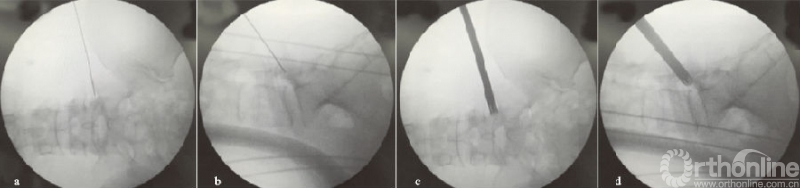

笔者认为中央型腰椎间盘突出症由于上关节突的天然阻挡(见图1a-b),要行走行神经根松解,需要做充分的关节突成形处理。中央型腰椎间盘突出症在穿刺及置入工作套管过程中,相对于其他类型的突出,椎管内压力大、神经向后或向外推挤明显,出现神经刺激症状及神经损伤的风险较高。因此,采用偏上、偏后将导杆及环锯置于上关节外侧骨面可避免直接或间接与神经根接触,这种置管方式能够减少神经刺激症状及损伤的风险,也不会破坏关节突的稳定性(见图1c-e)。

(a)(b)L4/5节段中央型突出的矢状位和横断位;(c)(d)环锯放置X线透视图;(e)术后腰椎CT三维重建图,红色方框示切除上关节突骨质范围;↖指突出椎间盘,IAP指下关节突,SAP指上关节突

图1 MRI示L4/5节段中央型椎间盘突出及环锯放置图